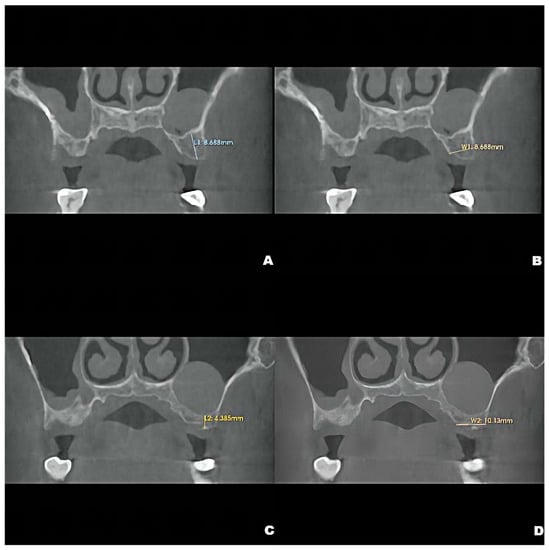

CBCT examinations were performed on CBCT scanners (3D Accuitomo, J. Morita Mfg. Corp., Kyoto, Japan) using the following parameters: 85-kV tube voltage, 5.0-mA tube current, field of view of 100 mm × 50 mm, and slice thickness of 1.0 mm. Dental CBCT scans showed that the local alveolar ridge width was optimal (8.688 mm for the left maxillary second premolar and 10.130 mm for the first molar) (Figure 1B,D); however, sinus augmentation was needed because the height of the residual alveolar bone in the posterior maxillary area was insufficient for implant placement. The patient was observed to have type 3 bone quality in the posterior maxilla on both sides, and according to our observation, there was no obvious thickening of the nasal mucosa in the pre-operative CBCT image. Notably, the height of the crestal bone between the sinus floor and the alveolar ridges of the left maxillary second premolar and first molar were 8.688 mm and 4.385 mm, respectively (Figure 1A,C). CBCT also revealed a homogeneously opaque, dome-shaped, and well-delineated lesion (volume, 3.795 mm3) in the left maxillary sinus (Figure 1 and Figure 2A); the lesion did not exhibit an epithelial lining. Prior to attending our clinic, the patient had consulted an otolaryngologist and received confirmation that no mucous cyst was present (no aggressive lesion appearance, significant bone resorption, or invasion of adjacent structures observed on radiologic imaging). Because the patient did not exhibit relevant symptoms, the otolaryngologist suggested conservative management of the pseudocyst. Accordingly, the treatment plan comprised osteotome sinus floor elevation, with simultaneous implant placement on the left side, in the presence of an antral pseudocyst.

Figure 1.

Preoperative CBCT showing the crestal height of L1 = 8.688 mm, (A), and local alveolar ridge width of W1 = 8.688 mm, (B), of the residual bone of the left maxillary second premolar and the crestal height of L2 = 4.285 mm, (C), and alveolar ridge width of W2 = 10.130 mm, (D), of the residual bone of the left maxillary first molar.